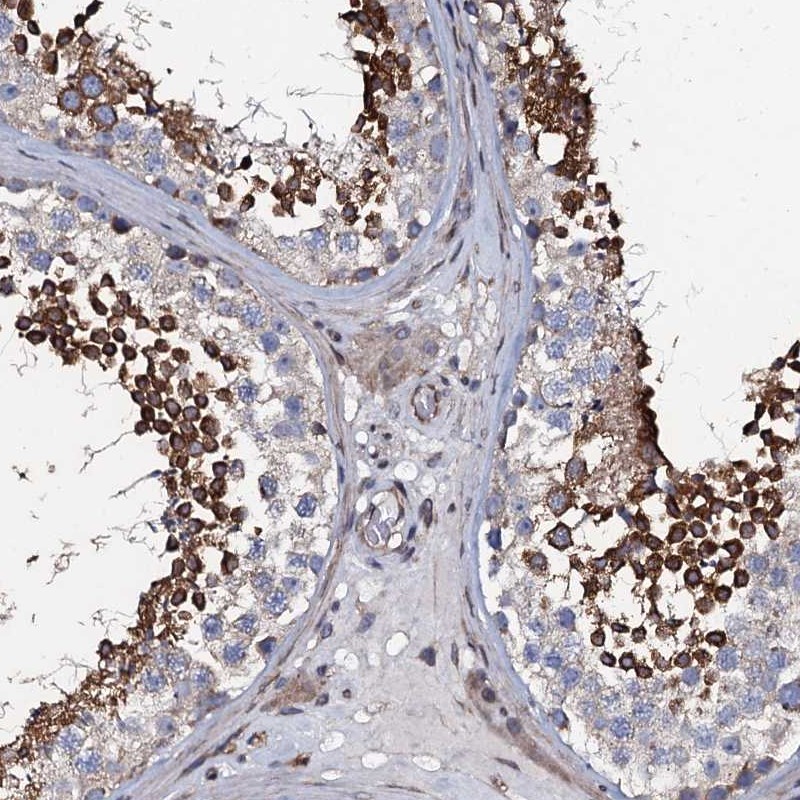

Immunohistochemical staining of human testis shows strong cytoplasmic positivity in cells of seminiferus ducts.